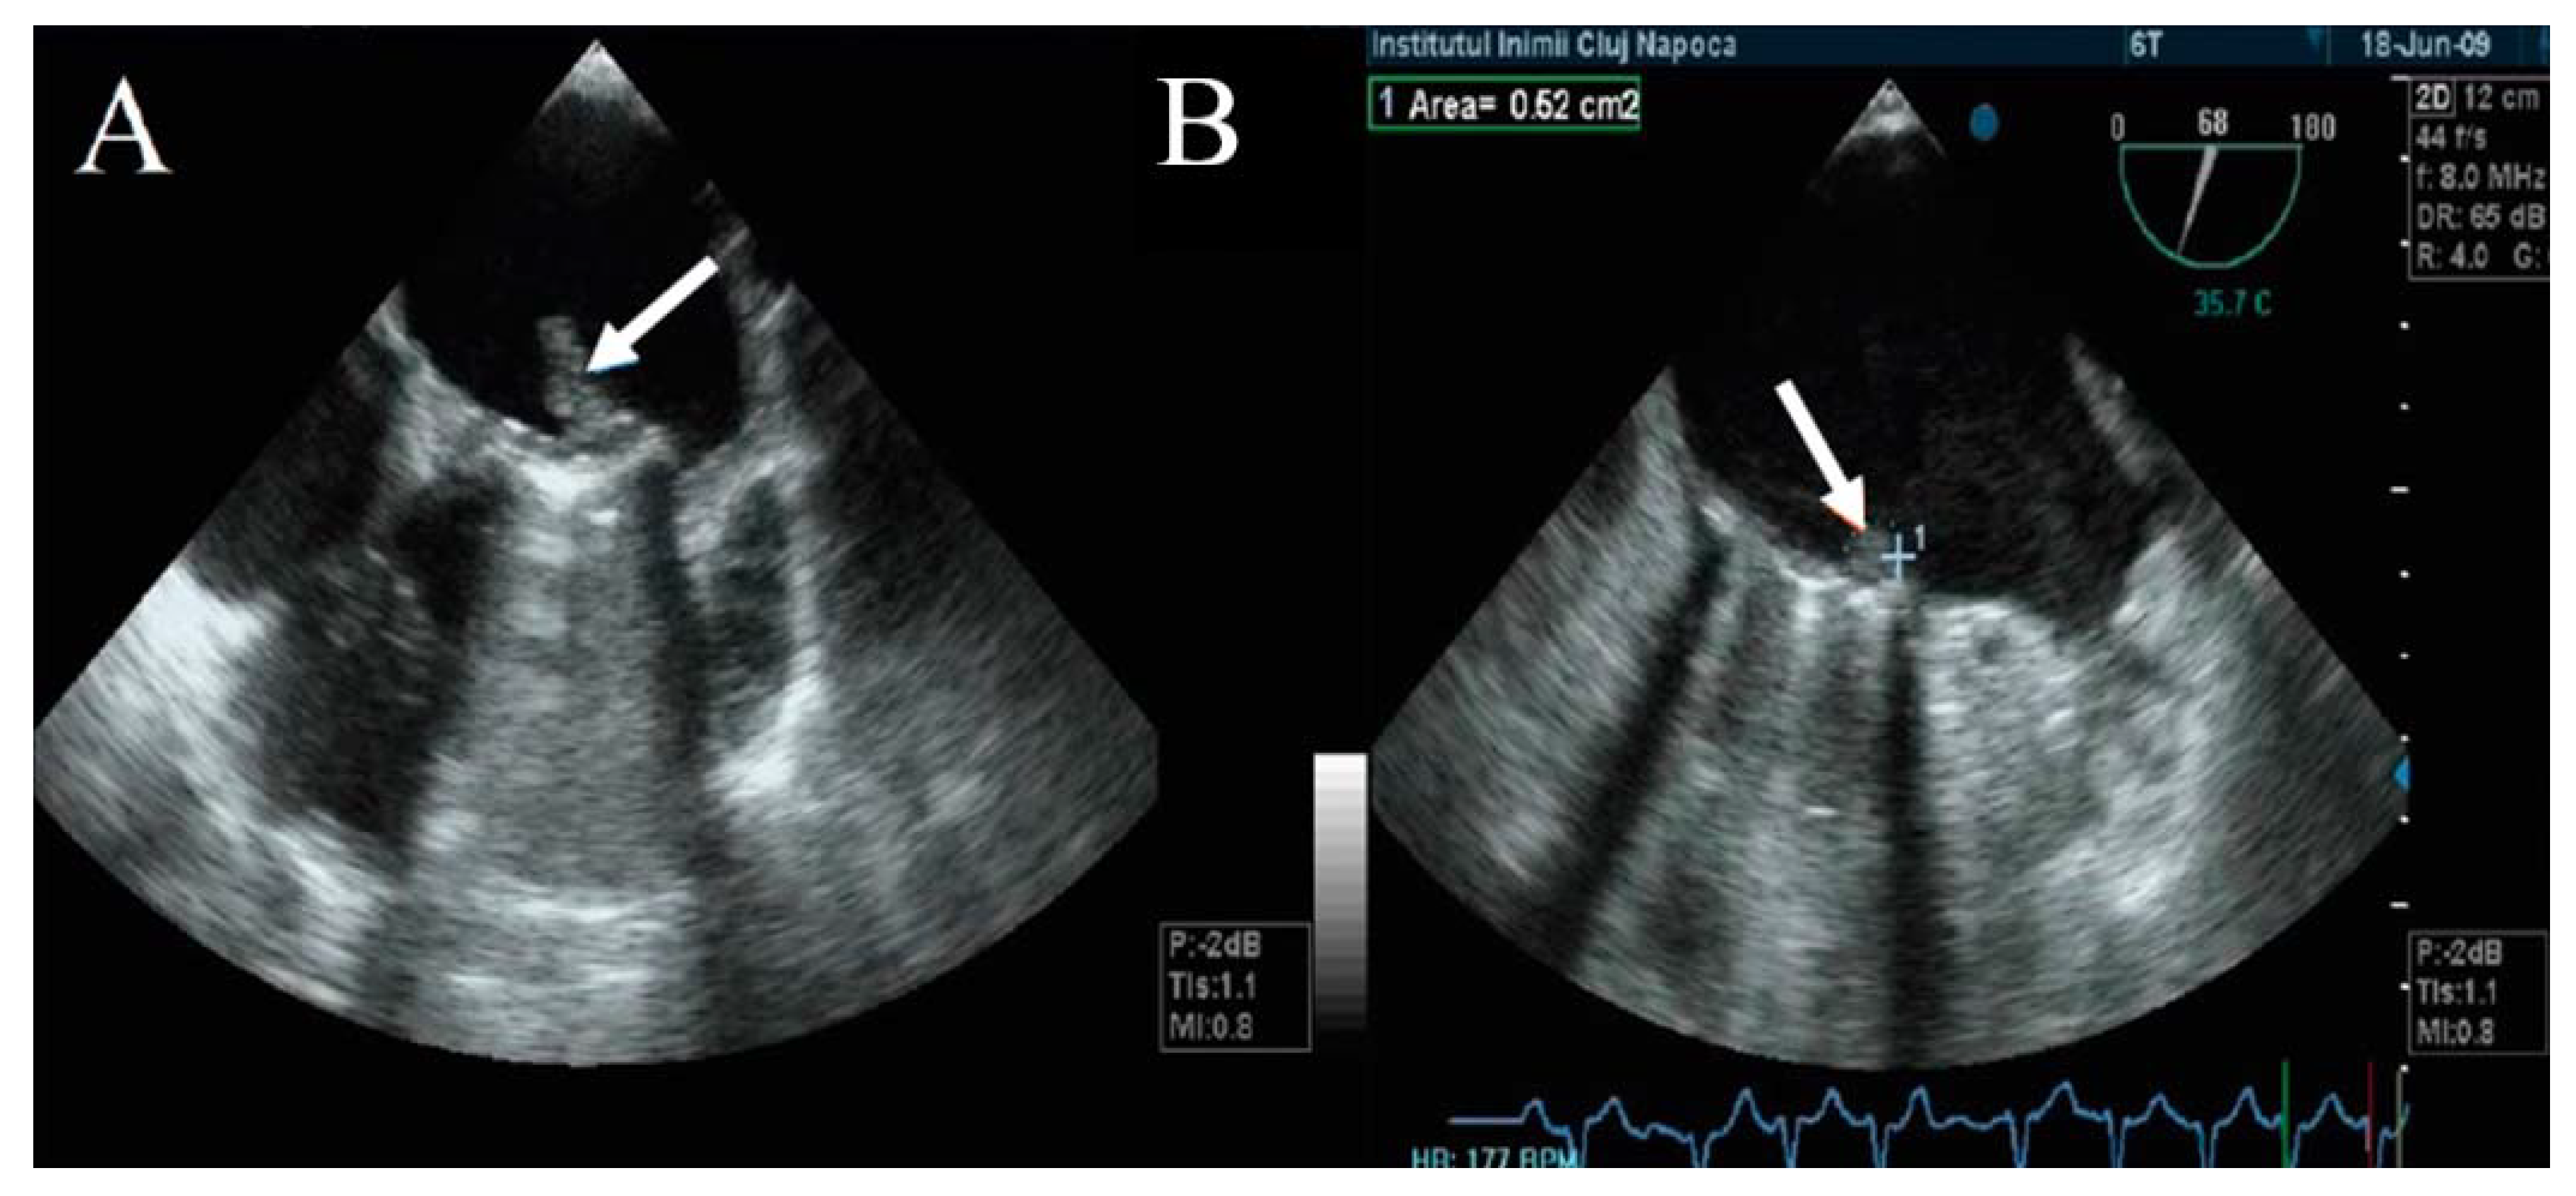

TEE has a major role in describing the size, mobility, and thrombus extension. It also has the ability to describe whether the thrombus is obstructive or nonobstructive, an essential aspect in the choice of therapeutic management (Figure 5) [1,21,22,25,27,28,29,30,31,32].

Figure 5.

TEE. Obstructive thrombus on the atrial side of mechanical mitral prosthesis (arrow).

The thrombus can be viewed as a polylobulated, amorphous mass with an echo density equal to the myocardium, an irregular contour, and variable movement that restricts the mobility of the prosthetic discs (Figure 6). The thrombus size defines the severity of the prosthesis obstruction. Generally, a recent onset of symptomatology with hypermobile obstructive thrombi is associated with hemodynamic instability and high embolic risk [21,22,23,24]. Tong et al. reported that a thrombus on left heart prosthesis with an area below 0.8 cm2 is associated with a lower risk of death, as well as embolic events after thrombolytic treatment [34].

Moreover, Ozkan M. et al. reported that a thrombus area above 0.9 cm2 that generates obstruction of the left heart prostheses increases the risk of embolism or death associated with a thrombolytic treatment. Based on this, the 2014 ACC/AHA guideline recommends emergency surgical treatment when the size of the thrombus on the left heart prosthesis is over 0.8 cm2. Thrombolytic treatment is recommended when the size of the thrombus is below 0.8 cm2, with a recent onset of symptoms and NYHA class I–II [10].

The embolic risk depends not only on the thrombus area, but also on the mobility and echogenicity of the thrombus. A recent onset of symptomatology and hypermobile thrombi with reduced echogenicity have a higher embolic risk than those that are hyperechogenic with reduced mobility (Figure 7) [35]. Moving images of floating thrombi on mitral prostheses are illustrated in Video S3 (Supplementary Material).

Moreover, 3D acquisitions can assist with the detection of silent thrombi that are present at the level of the prosthesis’ ring (Figure 8, panel B). In nonobstructive thrombi, where it is required to intensify anticoagulation and conduct rigorous monitoring, 3D TEE has a higher diagnostic value than 2D TEE [23,24,25,36,37,38,39].

Figure 8.

3D TEE with en face reconstruction of the mechanical mitral prosthesis with thrombus. (A) On disc (arrow). (B) On ring (arrow).